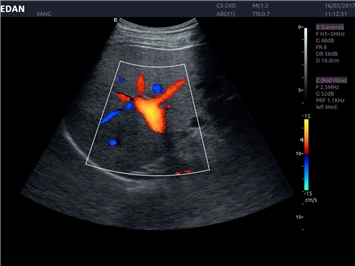

• Кардиологических исследований

Энергетический допплер:

Да

Постоянно-волновой допплер: